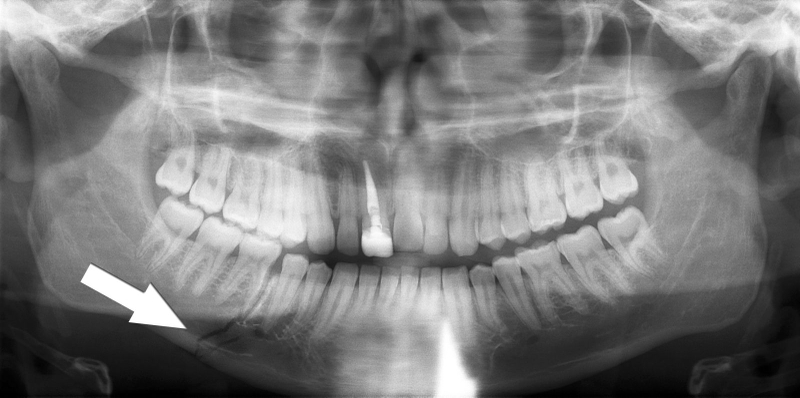

Để chẩn đoán chính xác hơn, các loại phim có thể được chỉ định chụp bao gồm:

Chụp X-quang phát hiện tổn thương xương hàm dưới